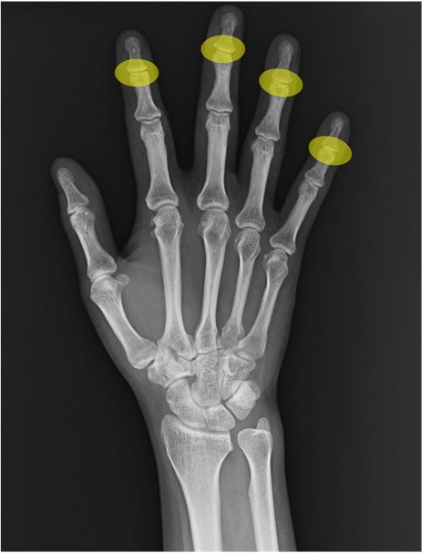

DIP関節(distal interphalangeal joint)

第2~5指の遠位指節間。末節骨基部の骨硬化・骨棘や石灰化沈着などを確認。